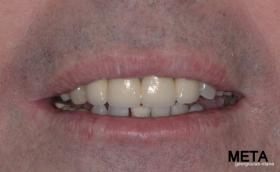

Ο ασθενής  προσήλθε στο ιατρείο μας θέλοντας να βελτιώσει την εμφάνιση των πρόσθιων δοντιών του και να αποκαταστήσει την υγεία κ την λειτουργία όλου του στόματος. Πραγματοποιήθηκε περιοδοντική θεραπεία κ ενδοδοντικές θεραπείες (απονευρώσεις) όπου κρίθηκε απαραίτητο και στη συνέχεια τοποθετήθηκαν 3 εμφυτεύματα, 2 δεξιά στις θέσεις του πρώτου κ δεύτερου γομφίου κ 1 αριστερά στη θέση του πρώτου προγομφίου. Κατά την  τοποθέτηση των 2 εμφυτευμάτων της δεξιάς πλευράς, πραγματοποιήθηκε κλειστή ανύψωση ιγμορείου με το σύστημα Piezotome-Intralift , τεχνική που εξασφαλίζει τη μικρότερη δυνατή επέμβαση κ τη μικρότερη μετεγχειρητική ταλαιπωρία (minimally invasive), καθώς κ αυξητικους παράγοντες PRF. Σε όλη τη διάρκεια της θεραπείας  ο ασθενής ήταν καλυμμένος τόσο αισθητικά όσο και λειτουργικά με προσωρινές μεταβατικές αποκαταστάσεις. 4 μήνες μετά την  τοποθέτηση των εμφυτευμάτων κ την οστεοενσωμάτωσή τους, ακολούθησε η τοποθέτηση των μόνιμων αποκαταστάσεων.